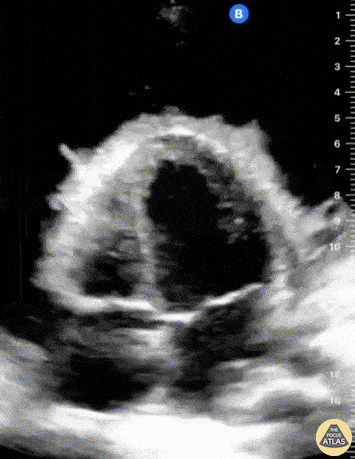

A young male presented with a 5-month history of signs and symptoms of heart failure. Apical four chamber view pictured here revealed a large pericardial effusion, most significant for the presence of fibrinous stranding. Fibrinous pericardial effusions are most commonly related to tuberculosis (worldwide) whereas malignancy and inflammatory/infectious processes are alternate possible etiologies. PCR of pericardial fluid went on to confirm Mycobacterium tuberculosis in this patient. Note: depth of this image was intentionally used to augment the view of the apex and presence of fibrinous strands. Gordon Johnson, @pdxfutebol Portland, Oregon